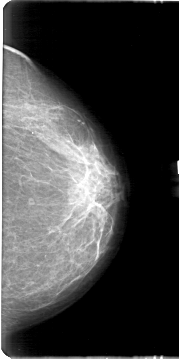

D_4166_1.LEFT_MLO

D_4166_1.LEFT_CC

LEFT_MLO LINES 5191 PIXELS_PER_LINE 2701 BITS_PER_PIXEL 12 RESOLUTION 43.5 NON_OVERLAY

LEFT_CC LINES 5371 PIXELS_PER_LINE 2671 BITS_PER_PIXEL 12 RESOLUTION 43.5 NON_OVERLAY